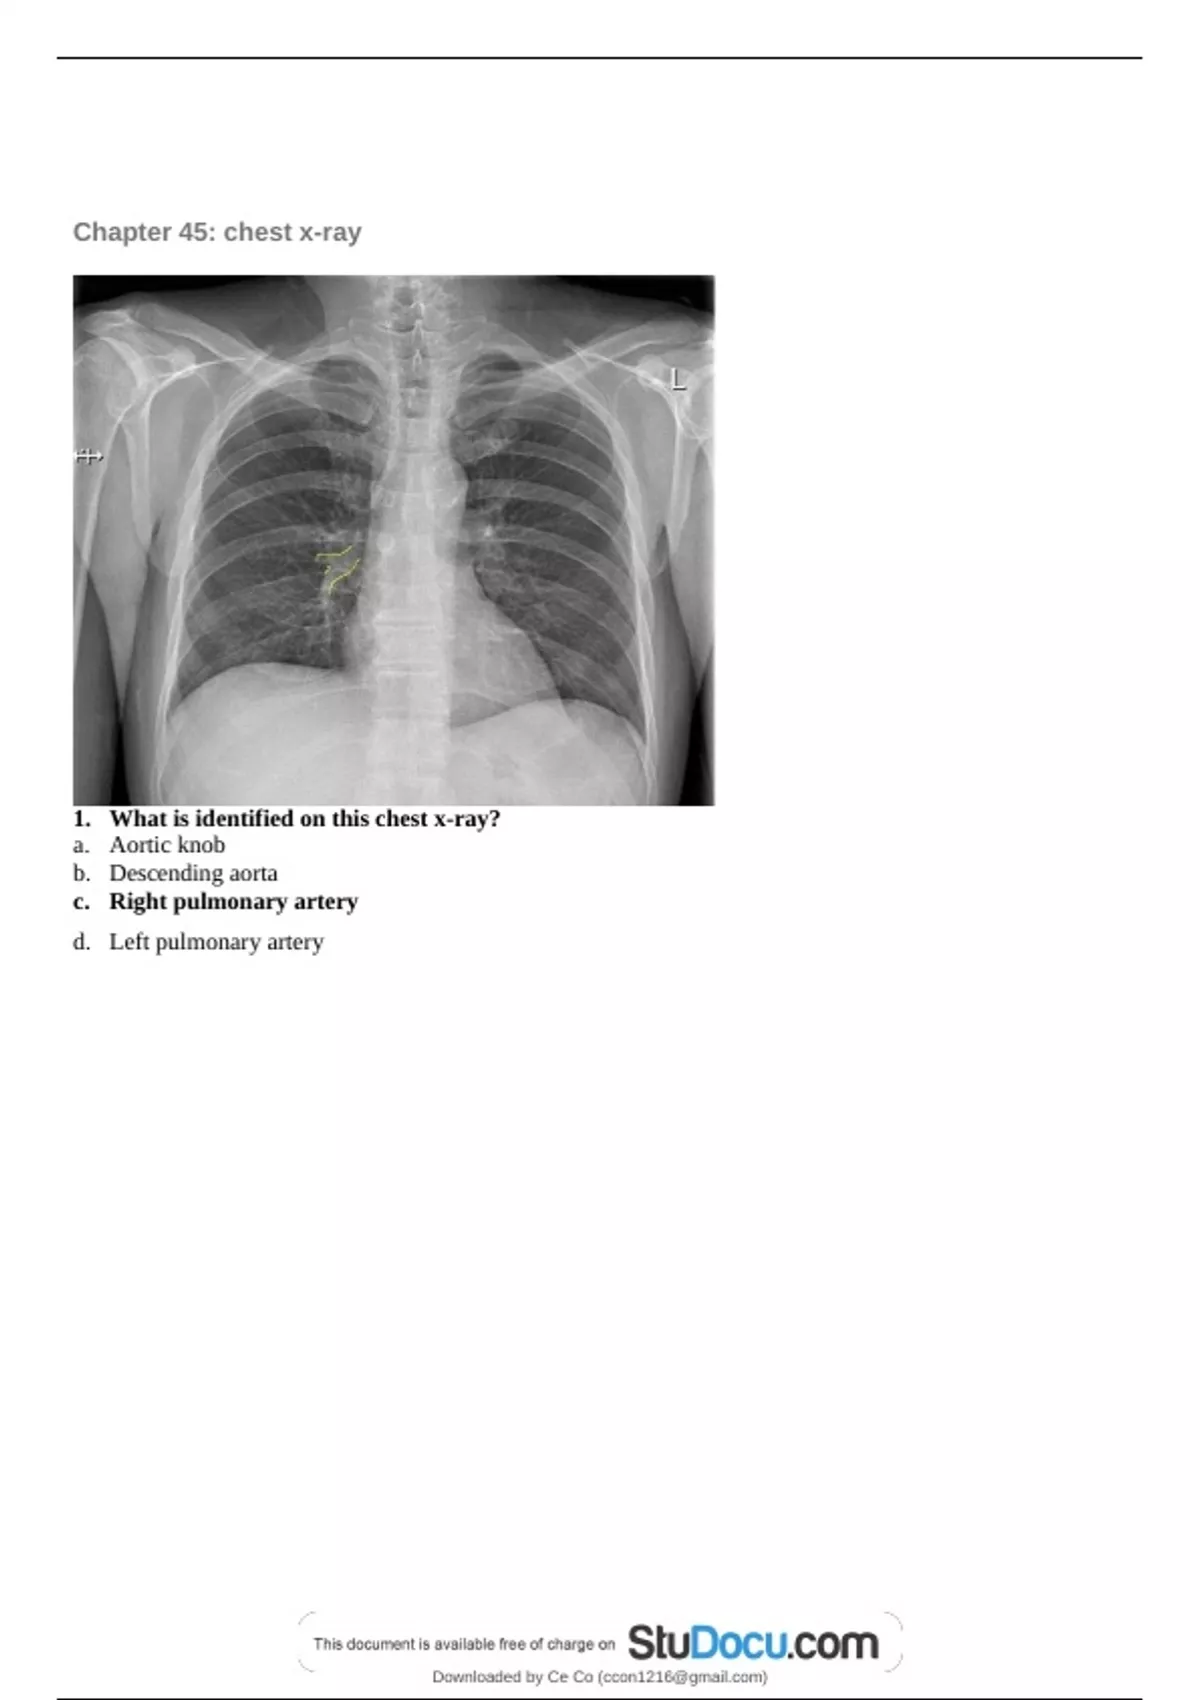

Chapter 45: chest x-ray

1. What is identified on this chest x-ray?

a. Aortic knob

b. Descending aorta

c. Right pulmonary artery

d. Left pulmonary artery